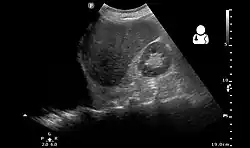

Ultrasonography may be used to detect hemothorax and other pleural effusions. This technique is of particular use in the critical care and trauma settings as it provides rapid, reliable results at the bedside.[23] Ultrasound is more sensitive than chest x-ray in detecting hemothorax.[25] Ultrasound can cause issues in people who are morbidly obese or have subcutaneous emphysema. When CT is unavailable in the current setting or the person cannot be moved to the scan, ultrasound is used.[3]

Pleural fluid sample from a hemothorax taken by thoracentesis

Although imaging techniques can demonstrate that fluid is present within the pleural space, it may be unclear what this fluid represents. To establish the nature of the fluid, a sample can be removed by inserting a needle into the pleural cavity in a procedure known as a thoracentesis or pleural tap. In this context, the most important assessment of the pleural fluid is the percentage by volume that is taken up by red blood cells (the hematocrit) A hemothorax is defined as having a hematocrit of at least 50%[6] of that found in the affected person's blood, although the hematocrit of a chronic hemothorax may be between 25 and 50% if additional fluid has been secreted by the pleura.[8] Pleural fluid can dilute hemothoraces in as low as 3–4 days.[5] The red blood cells in the effusion spontaneously break down.[11] Distinguishing the pleural fluid from blood by colour is impossible when the hematocrit value is over 5%.[3] For these reasons, even if there is a hematocrit value under 50%, further investigations can be done in order to figure out if there is a source of bleeding.[5] Hematocrit can be roughly calculated by dividing the red blood cell count of the pleural fluid by 100,000.[6] Thoracentesis is the test most commonly used to diagnose a hemothorax in animals.[28] Hemothorax can itself be a rare complication of thoracentesis if the intercostal artery is punctured.[29]